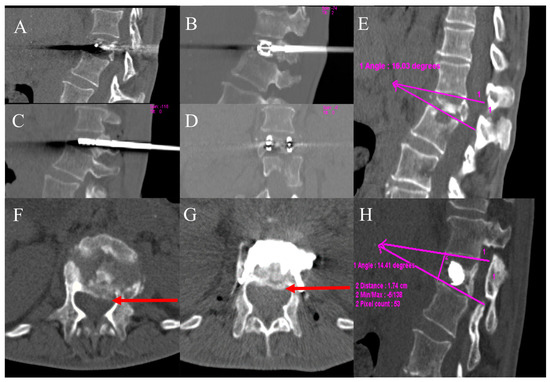

An immediate post-procedural no contrast-enhanced CT scan was performed to evaluate the results and any complications (Figure 1).

Figure 1. A 58-year-old male with a history of colon cancer with lumbar pain. (A,B) lateral fluoroscopic image—Axial CT image showed a pathological compression fracture of the superior endplate of the vertebral body of L3 with extension to the periosseous soft tissue (red arrow in (B)); (C,D) lateral fluoroscopic image ©—axial CT image (D); microwave antennae inserted coaxially through cannulae for ablation (green arrows); (E,F) lateral fluoroscopic image (E)—axial CT image (F); post-procedure control showed a correct expansion of the vertebra with a homogeneous distribution of cement into the vertebral body (yellow arrows). No procedural complications were observed.